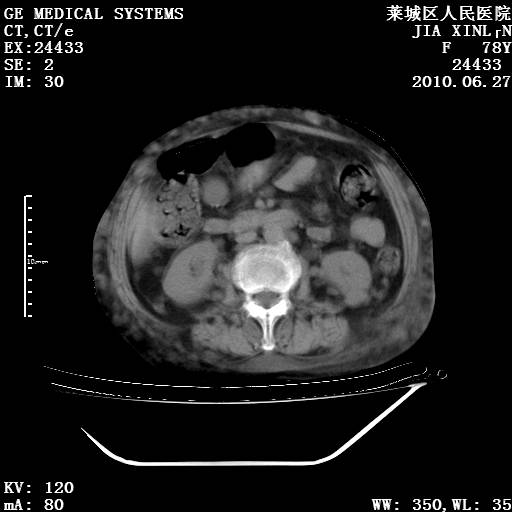

以下是引用胡宇在2010-7-2 19:11:00的发言:[br]神经纤维瘤的特点为:肿块呈多发性、数目不定,少的几个,多的可成百上千难以计数。小的如米粒,大的似拳头,甚至可达十数公斤以上。可松弛地悬挂于皮表,皱褶及松弛可致畸形明显。神经纤维瘤沿神经干的走向生长时呈念珠状,或蚯蚓块状形结节。此外神经纤维瘤皮肤可出现咖啡斑,大小不一,形如雀斑小点状,或大片状,分布与神经纤维瘤肿块的分布无关。肿瘤数目不多的患者,皮肤色素咖啡斑状沉着是纤维神经瘤的重要诊断之一。 本病多发于躯干,有时出现于四肢及面部,患者常合并许多疾病应予重视加以区别。 [br] [br] [br] [br]lyb999说 [br]